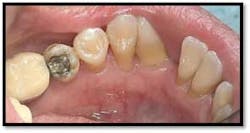

LR lingual post Tx and LL lingual post

Tissue is light pink, tight and firm. Pockets 1-3mm no BOP